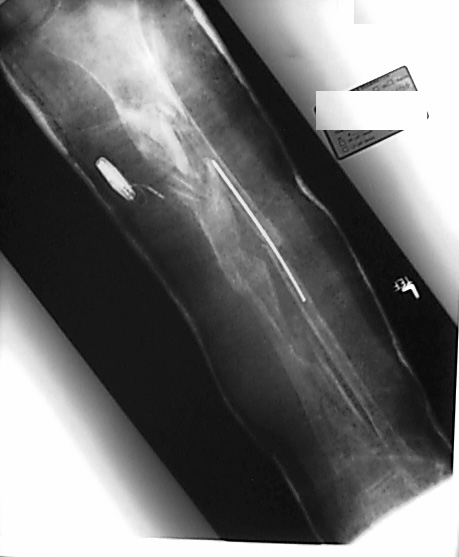

Case 1

Fifteen Month Followup.

Patient is 30 yo male 15 months status post severely comminutedtibia fracture (plateau, shaft, plafond) treated with ring fixator and freeflap - now one day s/p removal of the ring fixateur. The soft tissue envelopeis scarred but healed. Most of the fracture lines and fragments have healedbut there is gross motion 15 cm distal to the joint which was treated withbone graft and implantable electrical stimulator. The patient is partialweight bearing in a custom brace. Images obtained with Kodak DC50 digitalcamera.